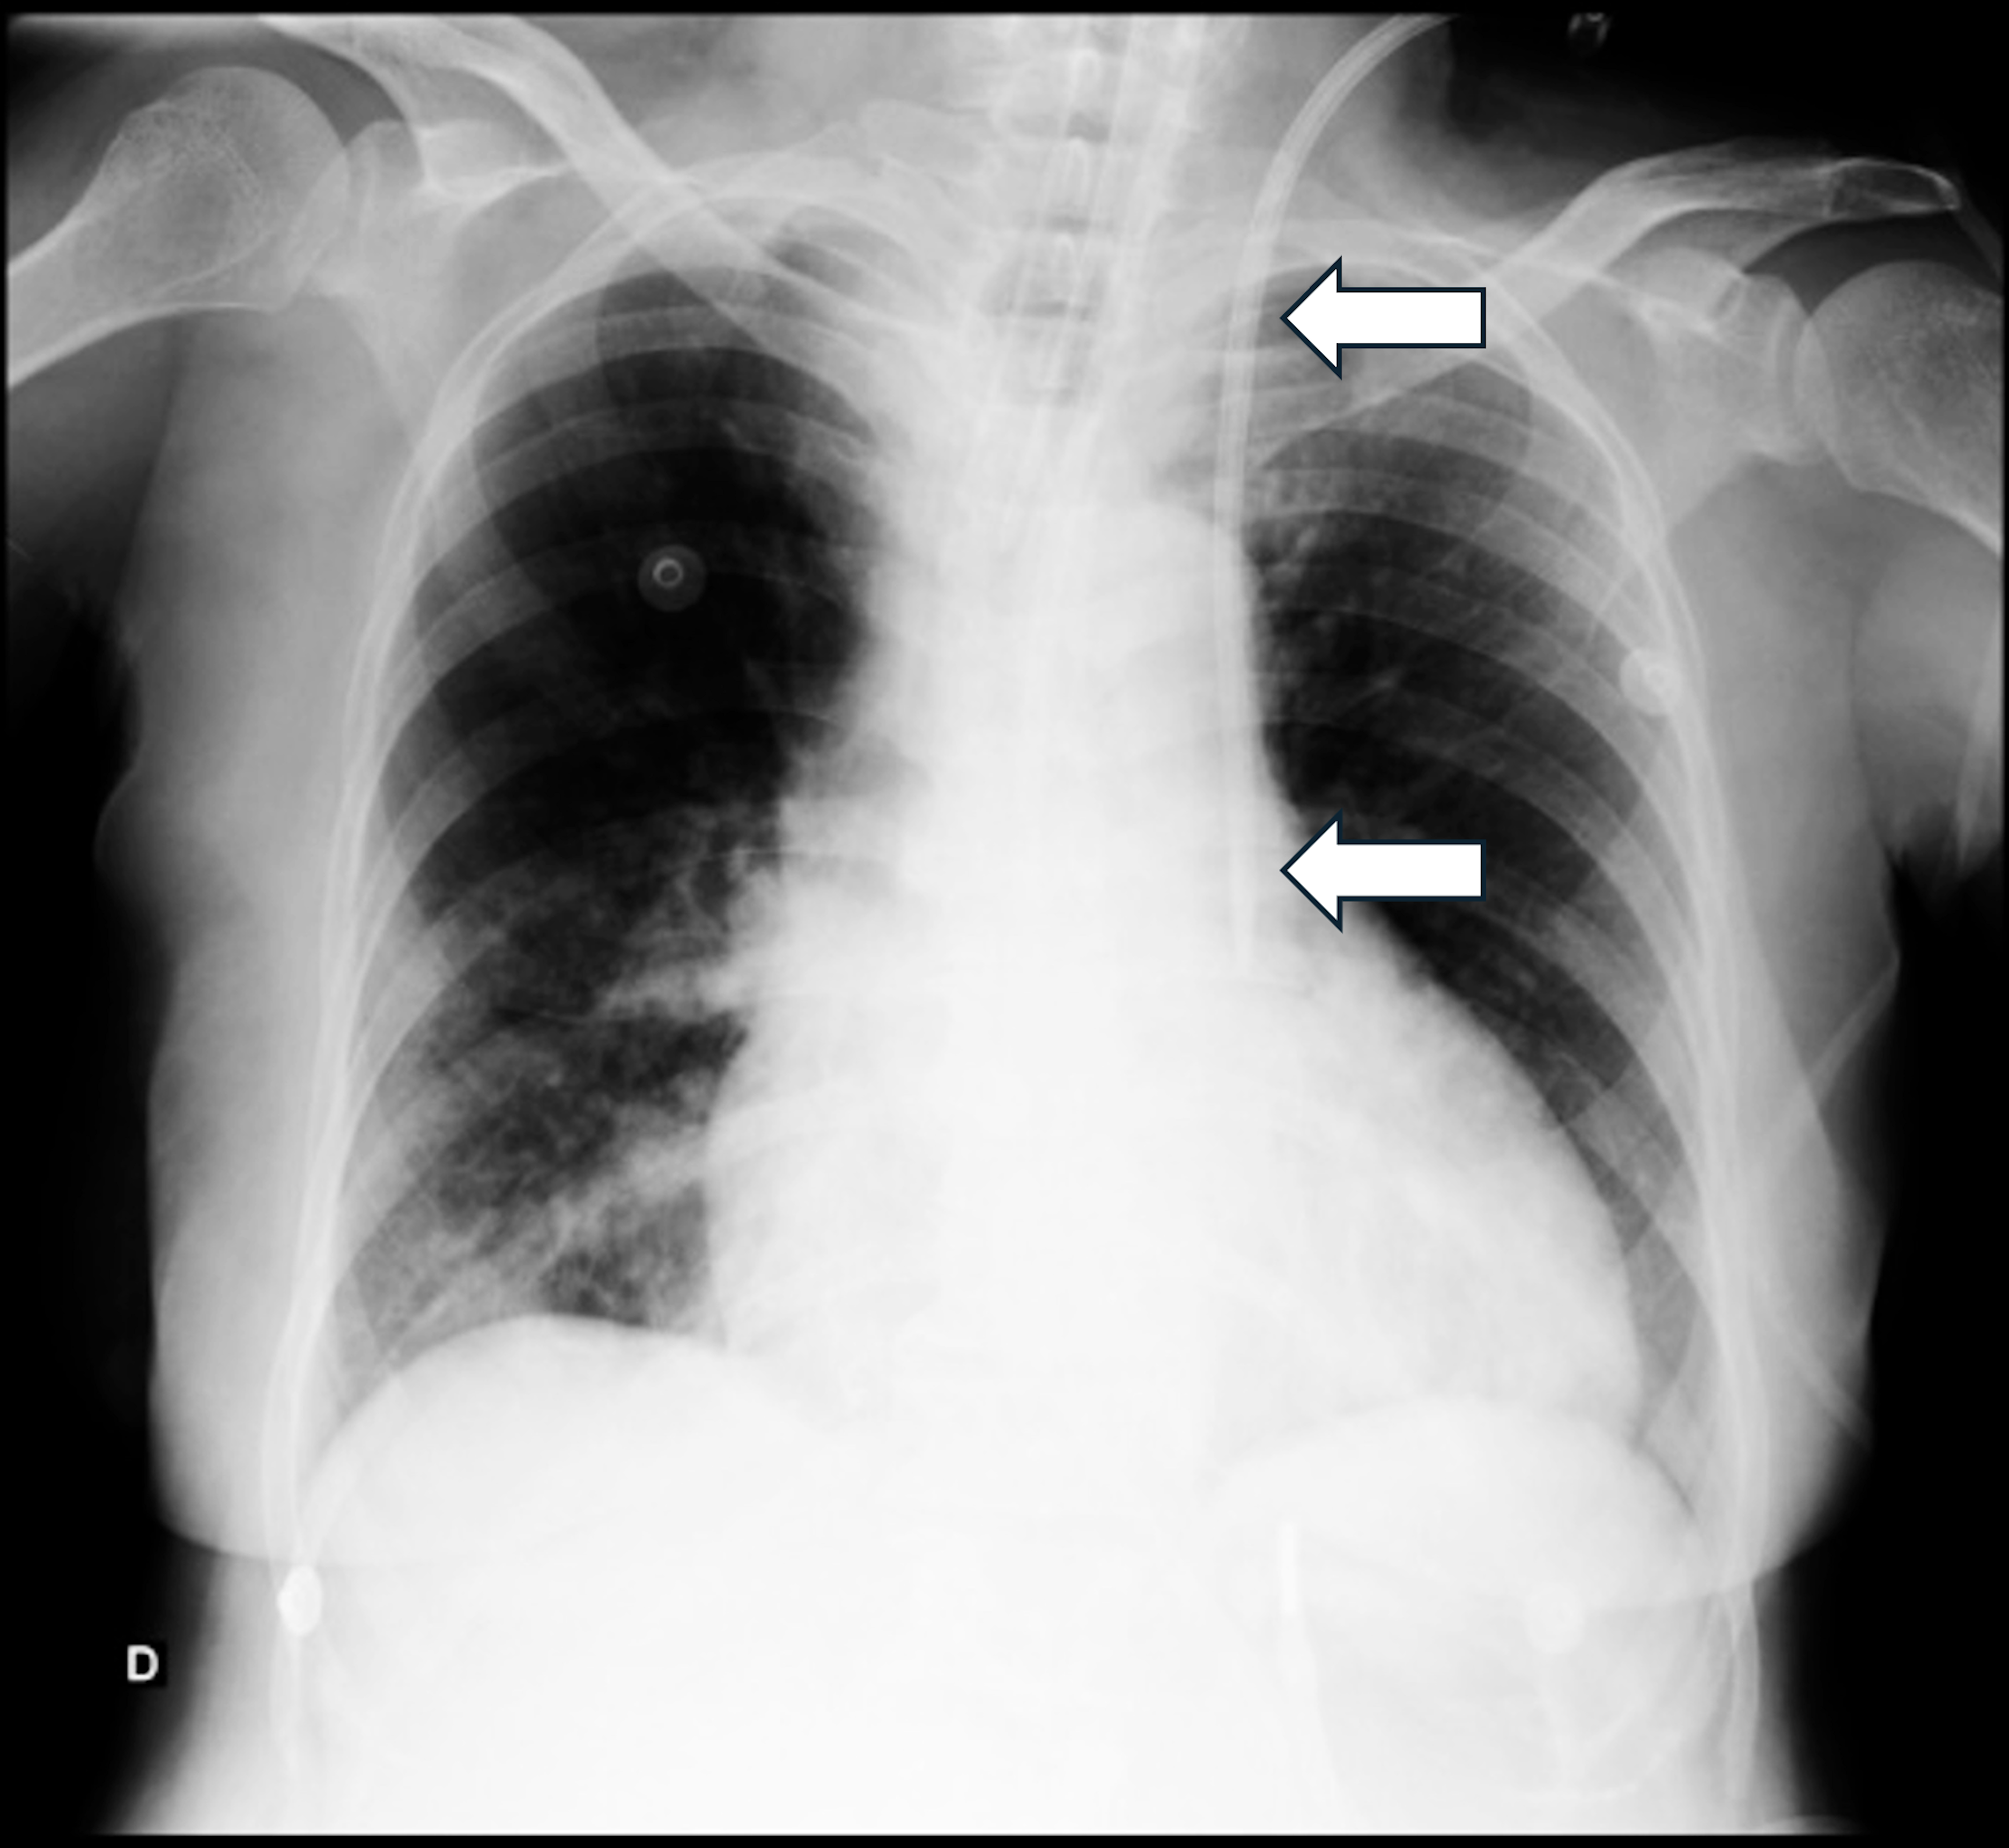

When Pulmonary Tuberculosis Leads to Pneumothorax: An Unusual Presentation

Catarina Bettencourt Giesta, Manuel d'Almeida, Sara Pires Ferreira